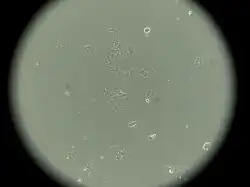

MCF-7 cells

MCF-7 cells have the following characteristics:[2][6][7][9][10][11]

This cell line retained several characteristics of differentiated mammary epithelium, including the ability to process estradiol via cytoplasmic estrogen receptors and the capability of forming domes.